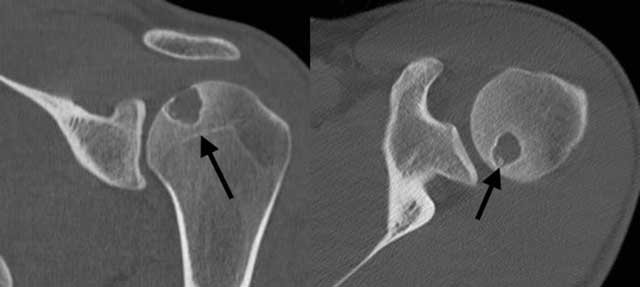

Figure 3

CT of the left shoulder. (A) Coronal reformatted image: the lesion does not reach the growth plate, which is already closed (arrow); (B) Axial plane image: a few small dense fragments can be seen in the lytic lesion (arrow): calcifications, confirming the presence of a chondroid matrix.